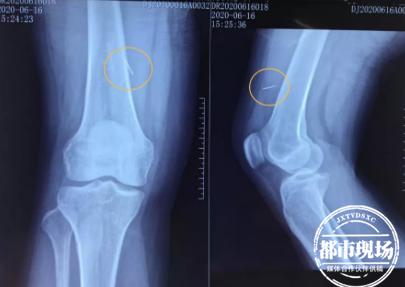

为求治,6月16日,付奶奶来到南昌市洪都中医院就诊。骨伤一科主任许振波接诊后,立即联系了麻醉一科伍剑锷主任,决定在局麻下,采用超声引导定位法为付奶奶取出断针。在两位主任密切配合下,仅15分钟,那根针头断端就被精准定位,安全取出。